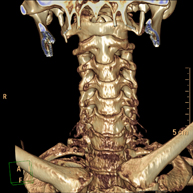

- TC Columna cervical

Prueba radiológica que consiste en obtener imágenes de las vertebras cervicales de alta definición anatómica mediante el empleo de un equipo de TC (Tomografía Computarizada). Indicaciones: cervicalgia sin/con irradiación a brazos, traumatismo.